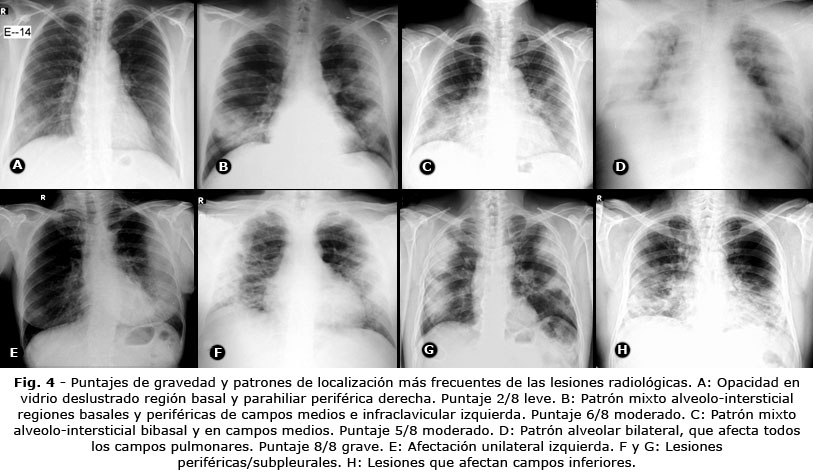

En relación con los patrones de localización, las lesiones bilaterales se presentaron en 772 casos para un 89,9 % del total, en 87 pacientes la afección fue unilateral, lo que representó el 10,1 %. Las lesiones periféricas/ subpleurales se presentaron en 573 pacientes (66,7 %) y las centrales en 286 para el 33,3 %. Fueron más frecuentes las lesiones localizadas en campos inferiores con 781 casos (90,9 %), seguido de 52 con afectación de campos medios (6,1 %) y en el 6 % los superiores (Fig. 4).